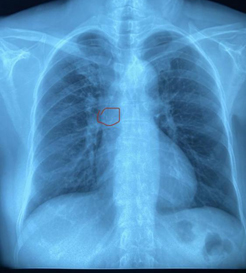

置管后X线显示导管位置达到理想位置